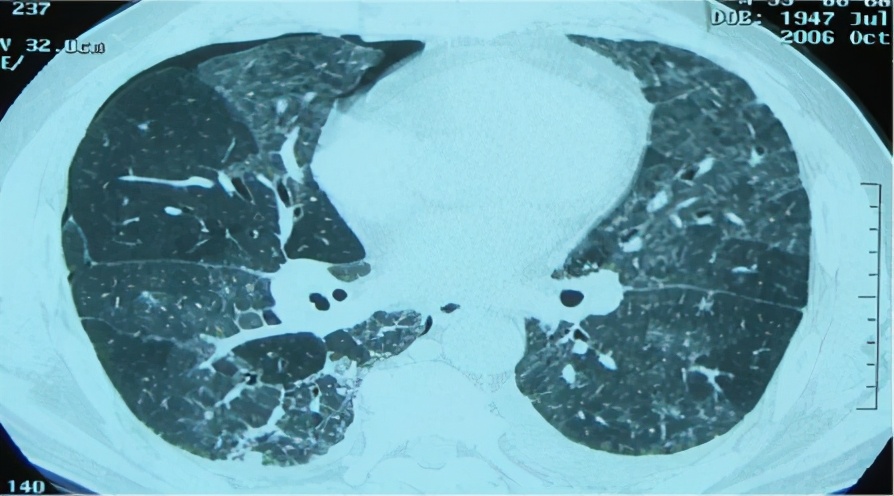

急性和亚急性过敏性肺炎的胸部CT的差距就比较明显,我们可以看到典型改变:小叶中心结节,边界不清,弥漫分布;轻症患者CT也可无明显异常;磨玻璃样/实变,片状或弥散,支气管血管束,下叶分布;肺气肿或马赛克征象。

胸部CT:不规则索条影、网格、结节(小叶中心)、磨玻璃;肺结构改变更明显,支气管扩张,蜂窝肺;肺皱缩(上叶)下叶代偿性肺气肿,但是无钙化和空洞;马赛克(主要见于亚急性/慢性);支气管血管束增重。

2)CT特点: 马赛克/气体陷闭、磨玻璃、细小结节、蜂窝肺、纵膈淋巴结肿大等最常见。

过敏性肺炎实际上是吸入抗原诱发的肺脏免疫炎性疾病,临床表现急、亚急性和慢性过程,以亚急性和慢性多见。目前倾向于按是否有纤维化进行分型,非纤维化型HP多指急性/亚急性,HRCT主要是小叶中心结节、斑片磨玻璃影、马赛克征。纤维化型多指慢性HP,HRCT还可见小叶间隔增厚,不规则粗、细网格,伴牵拉支扩,蜂窝等。病理特点为细支气管炎、不同类型不同程度的间质性肺炎(NSIP、OP、UIP)、肉芽肿。BALF:淋巴细胞增多,>40%。诊断主要是依据抗原及与疾病关系、HRCT、BAL-Lym↑。治疗为脱离抗原,酌情激素治疗。过敏性肺炎是一种可防可治的ILD,所以我们要提高认识,积极防诊治,改善病人生活质量。